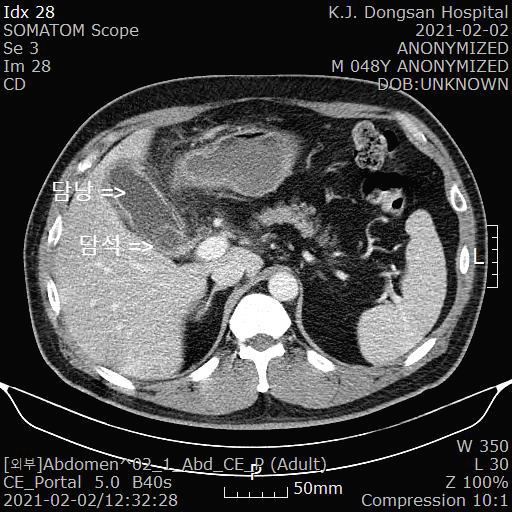

최근 다시 복통이 발생하여 2021.2.2일 낮에 경주 동산병원을 내원했고 동산병원에서 복부 CT를 시행했습니다.

위 사진은 동산병원에서 시행한 복부 CT 소견입니다. 담낭에 염증이 심하고 담낭내에 담석이 확인됩니다.